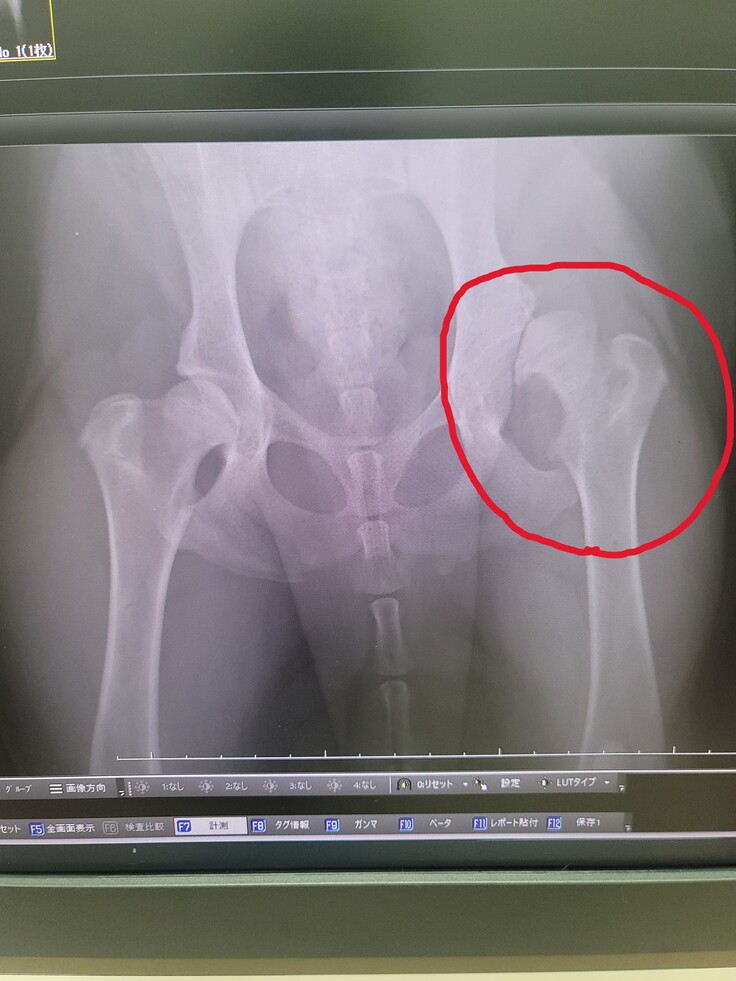

散歩をしている際らむねの歩き方に違和感を感じよく見るとおしりを大きく振って歩いており、そこまで気にしてはいませんでした。ちょうど3月に赤ちゃん検診がありお医者様に、現状の歩き方について相談したところ左後ろ足が「股関節形成不全」の可能性があると伝えられました。ただ生後6ヵ月の為、成長する上で改善するかもしれないと告げられたため体重調整をしながらしばらく様子を見ていました。

半日検査をしていただいた結果「股関節形成不全」と診断され、大型犬に多くほとんどが先天性の病気との事です。

らむねは早期発見ではありましたが、発見できた段階ですでに保存療法などでは治らない事がわかりました。

左足を使わないように動いていたため左足の筋肉も細くなっており、このままの状態だと歩行困難になってしまうと伝えられました。

らむね(ゴールデンレトリバー)の脚の手術(左後脚の人工股関節全置換手術)をします。